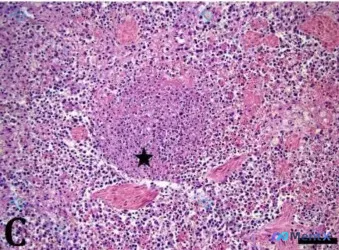

整理到一份猫科的病理讨论资料,感觉读片时的「思维陷阱」还挺典型的,放出来一起讨论。 基本信息: - 8月龄雄性英国短毛猫 - 背景提及「先天性结核病」可能 - 送检组织包含肺和脾脏 关键病理描述(原文给出): - 脾脏可见 无纤维包膜的坏死区(星号标记) 前期读片的分歧点: HE染色镜下曾被描述为「...